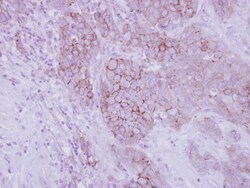

Opsin 3 Polyclonal Antibody, Invitrogen™

Recommended positive controls: 293T, A431, Jurkat, Raji. Store product as a concentrated solution. Centrifuge briefly prior to opening the vial.

Opsins are members of the guanine nucleotide-binding protein (G protein)-coupled receptor superfamily. In addition to the visual opsins, mammals possess several photoreceptive non-visual opsins that are expressed in extraocular tissues. This gene, opsin 3, is strongly expressed in brain and testis and weakly expressed in liver, placenta, heart, lung, skeletal muscle, kidney, and pancreas. The gene may also be expressed in the retina. The protein has the canonical features of a photoreceptive opsin protein. May play a role in encephalic photoreception. Strongly expressed in brain. Highly expressed in the preoptic area and paraventricular nucleus of the hypothalamus. Shows highly patterned expression in other regions of the brain, being enriched in selected regions of the cerebral cortex, cerebellar Purkinje cells, a subset of striatal neurons, selected thalamic nuclei, and a subset of interneurons in the ventral horn of the spinal cord.

Immunohistochemistry (Frozen), Immunohistochemistry (Paraffin), Western Blot